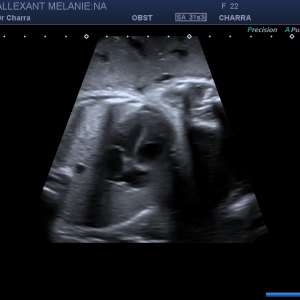

Suivi de votre grossesse avec réalisation des échographies recommandées, Prise en charge des IVG medicamenteuses (en lien avec la maternité de Beaune), infertilité, prise en charge des douleurs pelviennes (endométriose par exemple)

Suivi Echographique seul lorsque le suivi clinique est assuré par un autre professionnel de santé

Diplômée en Echographie foetale et Gynécologique

Diplômée en Médecine Foetale

Agrément National pour la réalisation des échographies du Premier Trimestre de grossesse